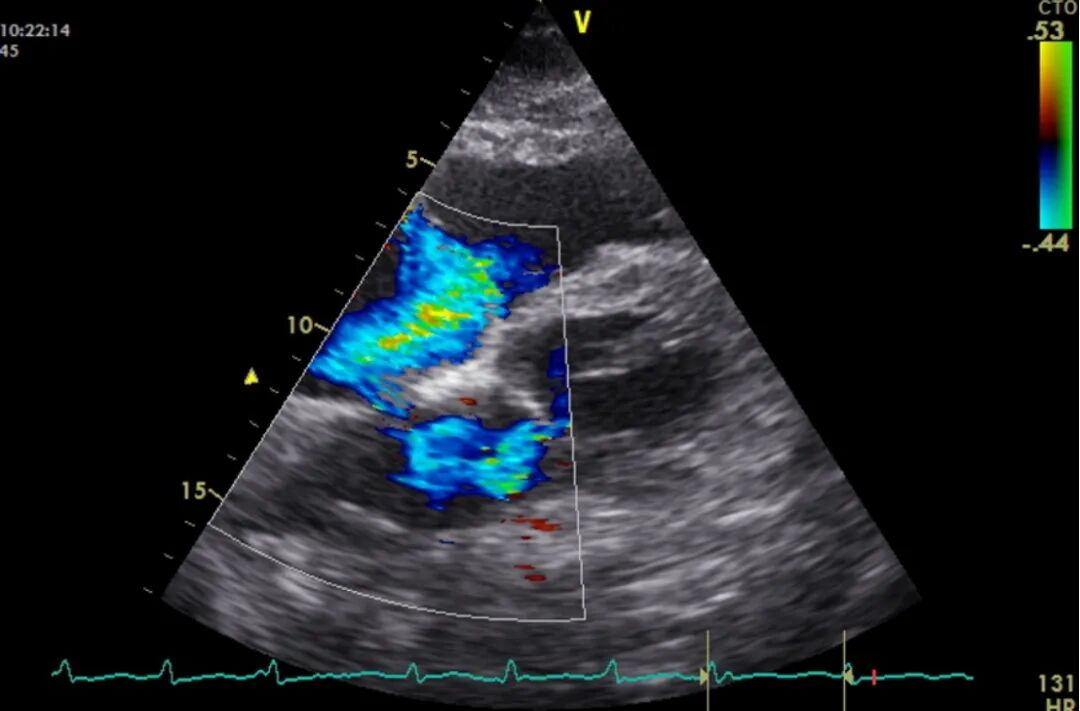

入院后常规完善心脏超声:LA 32 mm,LVd 41 mm,RV 16 mm, EF 68%,二尖瓣重度反流,未见明显赘生物,三尖瓣少量反流。结合患者反复发热病史,双肺影像学表现,考虑患者可能为急性左心衰。进一步完善经食管超声心动图(TEE),可见患者二尖瓣脱垂。

因此,患者以发热、呼吸困难为主要表现,伴气道内血性分泌物,肺泡出血也可出现类似的影像学表现,同时新发二尖瓣大量反流,不除外亚急性感染性心内膜炎或其他原因引起二尖瓣脱垂。患者虽然以呼吸衰竭起病,但支持方式应选择V-A ECMO。经手术治疗,患者顺利脱机出院。